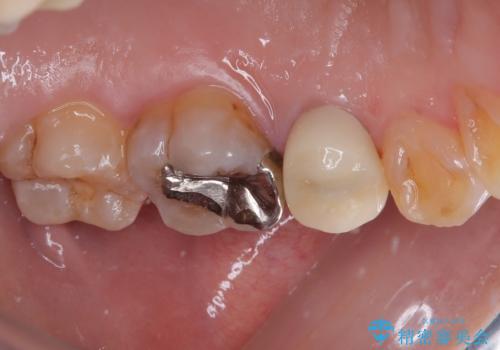

仮歯に替えた上で、速やかにオールセラミッククラウンにて補綴治療を行うこととしました。

銀歯を外したところ、土台にほとんどむし歯はなかったため、土台のやり替えを行うことなく、セラミッククラウンを装着しました。